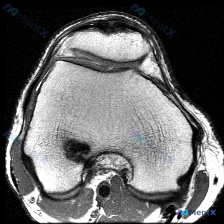

今天分享一份踝关节MRI的读片讨论,影像提示存在软骨异常,我们一起来梳理一下完整的分析思路。 病例影像基本信息 这是一份踝关节MRI冠状位T2加权图像,整理核心影像发现如下: 1. 骨骼系统:胫骨远端、距骨骨皮质连续性无中断,骨髓腔无明显弥漫性高信号,无明确急性骨髓水肿或骨挫伤 2. 关节与软骨:胫...